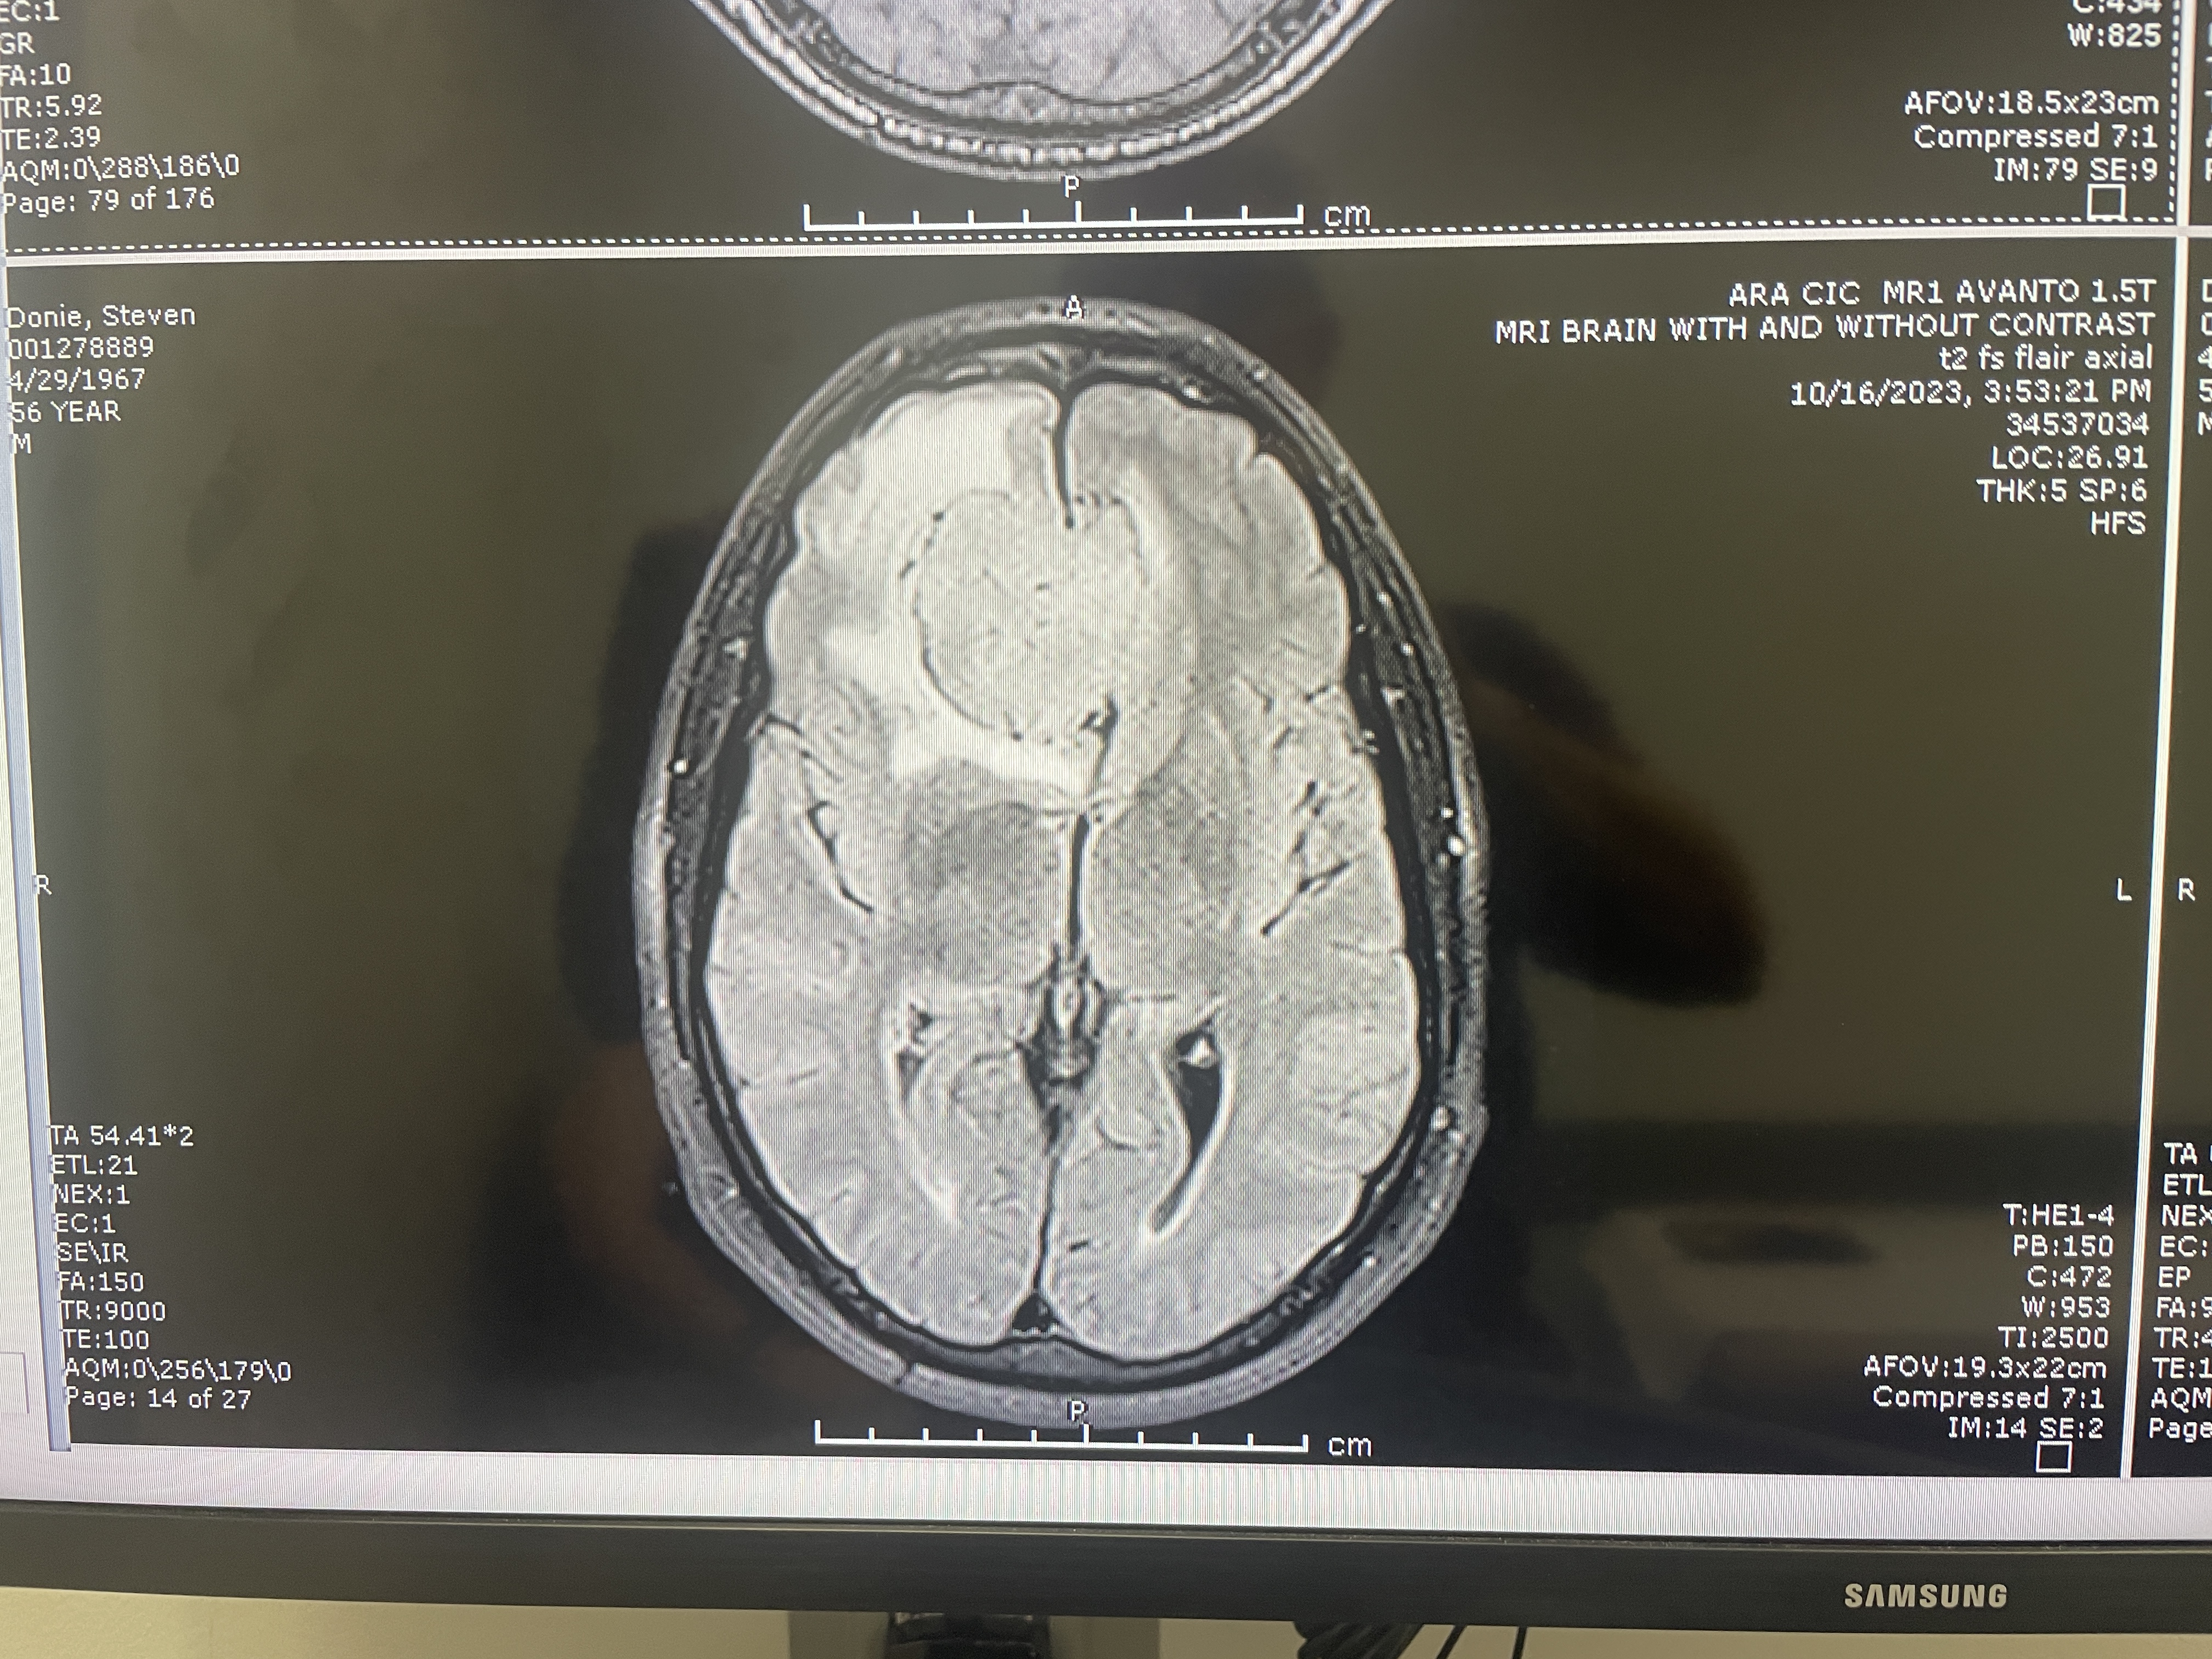

Another MRI top view